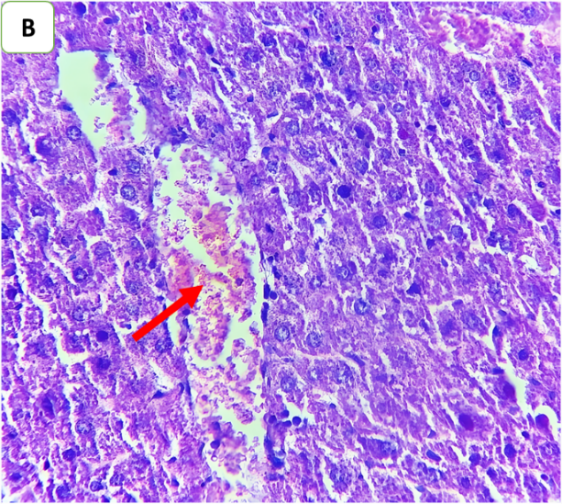

Histopathological examination was performed to evaluate the degree of hepatic injury 24 h after CLP. Compared with those in the sham group, the liver tissues in the CLP and CLP+DMSO groups were significantly damaged. Conversely, histopathological analysis of the liver in the CLP+ertugliflozin group revealed a slight degree of necroinflammation and steatosis (fig. 5, fig. 6). Fibrosis was not detected in any of the study groups.

Fig. 6: Effects of ertugliflozin on histopathological findings (6 animals in each group): A. CLP group: animals underwent CLP-induced sepsis, with a necroinflammatory grade of 3, liver tissue with vascular congestion (red arrow), hepatocytes ballooning (blue arrows), apoptotic cells (green arrow) and steatosis (yellow arrows). B. Sham group: animals in this group were anaesthetized only and then laparotomized without the induction of sepsis by CLP, and the necroinflammatory grade was zero liver tissue with vascular congestion (red arrows). C. CLP+ertugliflozin group: animals were intraperitoneally injected with ertugliflozin (20 mg/kg) 1 h before CLP, the necroinflammatory grade was zero, and vascular congestion occurred (red arrow). D. CLP+DMSO group: animals were intraperitoneally injected with DMSO (vehicle for ertugliflozin) 1 h before CLP, the necroinflammatory grade was 2, and the liver tissue exhibited mild inflammation (black arrow). Vascular congestion (red arrows). A and BandCandD X 400, HandE staining